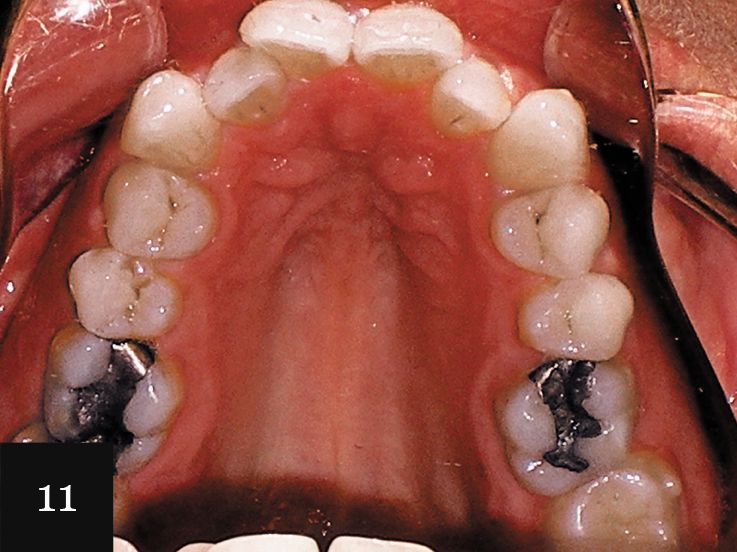

This treatment was performed on a male patient in his early 40s (Fig. 9). The patient had an omega-shaped upper arch, as seen in Fig. 10.

An impression was taken that successfully captured the complex crowding and narrow omega arch (Fig. 11), and the patient was treated with 28 aligners over 14 months. This case also illustrates use of the clear aligners as whitening trays, with the final result showing a smile that is not only straight, but also much brighter (Figs. 12-14).